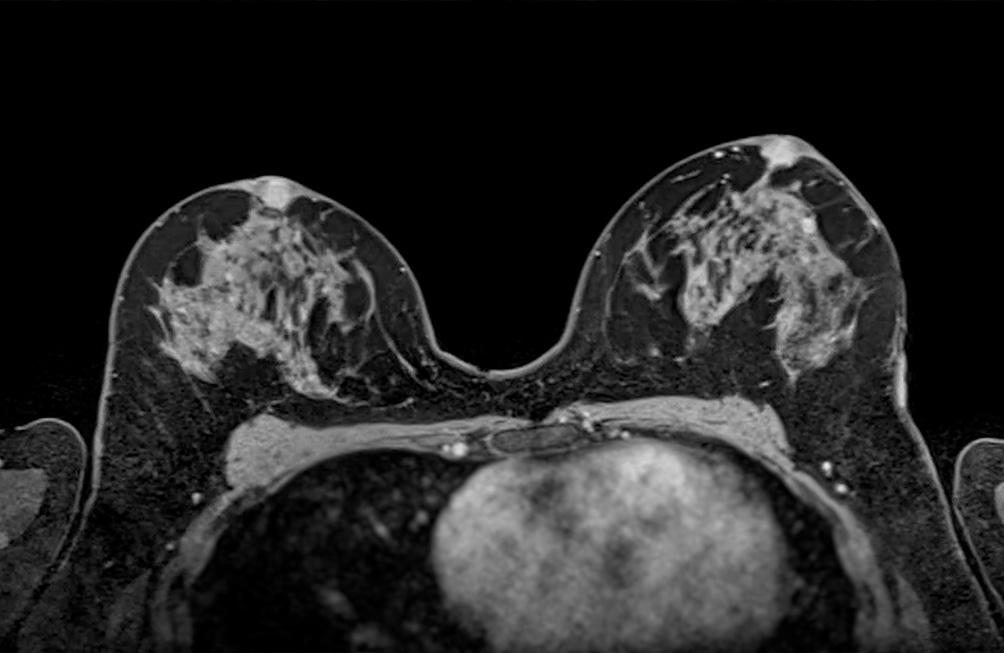

L'IRM mammaire est une méthode sûre et non invasive, réalisée afin d'assurer un diagnostic précis et un suivi adapté.

- D'une détection et caractérisation de lésions suspectes : lorsqu'une anomalie est détectée lors d'une mammographie ou d'une échographie, l'IRM peut aider à mieux visualiser la nature de la lésion, notamment pour différencier une tumeur bénigne d'une tumeur maligne.